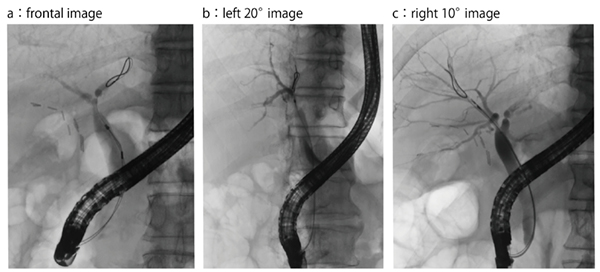

●症例5:肝門部領域胆道がん(60歳代、男性)

本症例は、正面視では確認できる左右分岐部が(図10 a)、Cアームを左方向に20°回転させると見えなくなり(b)、右方向に10°回転させることで明瞭に視認可能となった(c)。CT画像を確認したところ、この患者の腹腔内脂肪が多く、腹臥位で肝臓が腹腔内脂肪で圧迫されることにより角度が変わっていることが判明した(図11)。このように肥満の強い症例では注意が必要である。

図10 症例5:肝門部領域胆道がん(60歳代、男性)

図11 症例5:CT画像を用いた胆管枝角度の推定